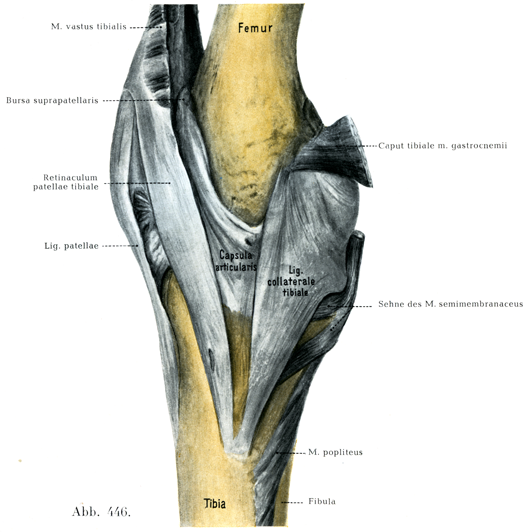

[図446]右の膝関節 内側からみる(3/4)

2. ,3. 脛側および腓側膝蓋支帯Retinacula patellae tibiale, fibulare(図446, 447)は膝蓋骨および膝蓋靱帯に平行して走っている.

4. 内側側副靱帯Lig. collaterale tibiale(図446)は大腿骨の内側上顆から起って,脛骨の内側縁と後縁につく.

この靱帯には前後の2部が区別され,前部の方が後部より長く,後部は内側半月の後縁までしか達していない.長い方の前部は半膜様筋の主停止部を被い,脛骨顆の下方で脛骨が急に細くなった部分を橋わたししているので,この靱帯の下にある組織をとり去ると,狭いすきまがみとめられる(図451).

1. 膝上嚢Bursa suprapatellarisは大腿骨の膝蓋面

の上方にあって,大腿四頭筋に被われ,たいてい関節腔と広いつながりをもっている.しかしこのつながりは狭いことがあり,まれには全く欠けていることもある(図446, 449, 450)